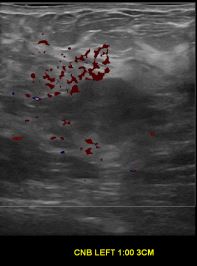

상기환자는 외부검사상 조직검사 권유받고 내원하신 40대 후반

여성분으로 의심스러운 좌측유방혹 조직검사 시행해 유방암으로 진단되었습니다